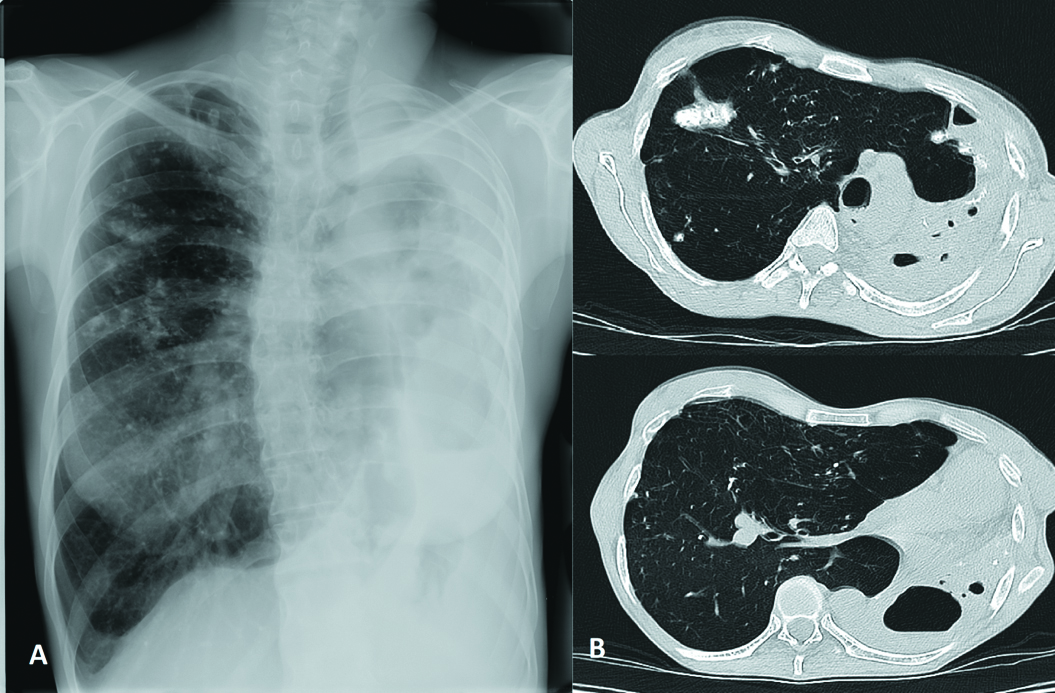

Upon admission (25.03.2021), X-ray and CT of the chest organs were performed (Fig. 1).

Figure 1. X-Ray (A) and CT of the chest organs (B) at admission, where A – displacement of the mediastinal organs (trachea, heart) to the left; B – large upper anterior pulmonary hernia, large foсus in S2 of the right lung, destroyed left lung.

The study of the X-ray and CT of the chest organs on admission revealed the following: the left lung is considerably smaller in volume, airless parenchyma, visualized lumen of the bronchi. The multilocular air cavity of the pleural empyema is located in the posterior costal section on the level of fourth to eleventh ribs, with low level of fluid and multiple small bronchopleural fistulas. On the left at the level of the second intercostal space, an encysted air cavity (size: 1.8х1.4х2.4 cm) with fluid. The mediastinum organs are shifted to the left and rotated. In the right lung, overexpanded for compensation, there are scattered multiple tuberculomae and dense partially calcific loci of various sizes. Probable presence of a small destructive air cavity in the shallow tuberculema located in the S5 under the pleura along the left parasternal line. Pulmonary mediastinal hernias are visualized: anterior superior up to the left anterior axillary line, left posterior in the section between the left paravertebral and scapular line. The volume (V3) of the hernia of the anterior mediastinum of the right lung is 740.65 cm3, and of the hernia of the posteroinferior mediastinum, 379.97 cm3. Conclusion: CT signs of pleural empyema on the left with bronchopleural fistulas, multiple tuberculomae of the right lung. Mediastinal pulmonary hernias of the right lung (Fig. 1).